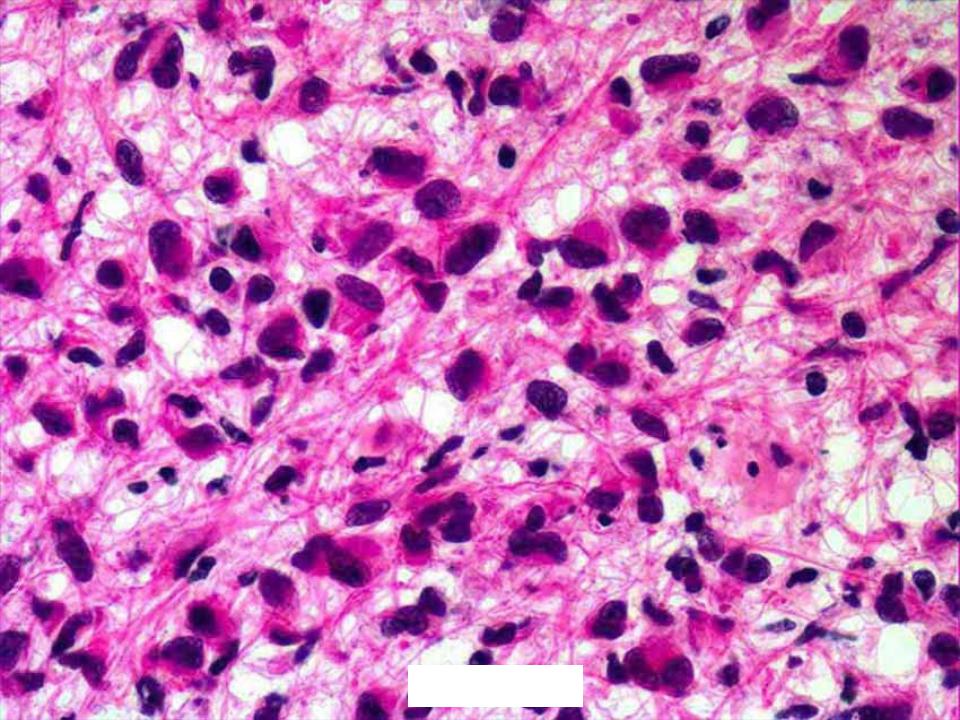

Микрофотографии гистологии глиобластомы головного мозга